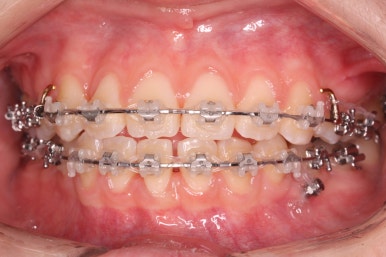

부산교정 키다리아저씨치과에서 장치를 부착하고 교정치료를 시작하였습니다.

이번에 부착한 장치는 엠파워클리어라고 하는 자가결찰 세라믹 장치입니다. 흔히들 클리피씨 장치로 많이 알고 계신 장치가 바로 자가결찰 세라믹 장치인데요.

자가결찰 세라믹 장치 중 또 다른 하나가 엠파워 클리어입니다. 클리피씨는 일본제품, 엠파워 클리어는 미국제품으로 제조회사가 다를 뿐 큰 분류에서는 비슷한 장치라고 보시면 되겠습니다.

가지런하게 하는 작업을 계속 합니다.

또한 왼쪽 위 작은 어금니 하나를 추가로 발치했습니다. 치아 갯수를 맞출 목적 + 우측으로 쏠린 앞니의 중앙을 개선하기 위함 입니다.

이제 어느 정도 치열이 가지런해졌습니다. 앞으로 해야 될 단계는 앞니 틈을 줄이고, 이 뽑은 자리 틈을 줄이면서 중앙선을 개선하고 아래쪽 어금니를 앞으로 당겨오면서 교합을 맞추며 앞니 갯수를 맞춰줍니다.